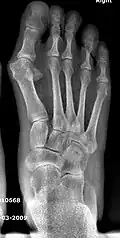

![]() Fig. 8a. Painful hallux valgus and metatarsus primus varus deformity recurrence of left foot after osteotomy surgery | |

- For recurrence correction after osteotomy procedure (Fig. 8)

Late deformity recurrence can happen after osteotomy (bone-breaking) procedures because osteotomy surgeries do not specifically stabilize first metatarsal bone.